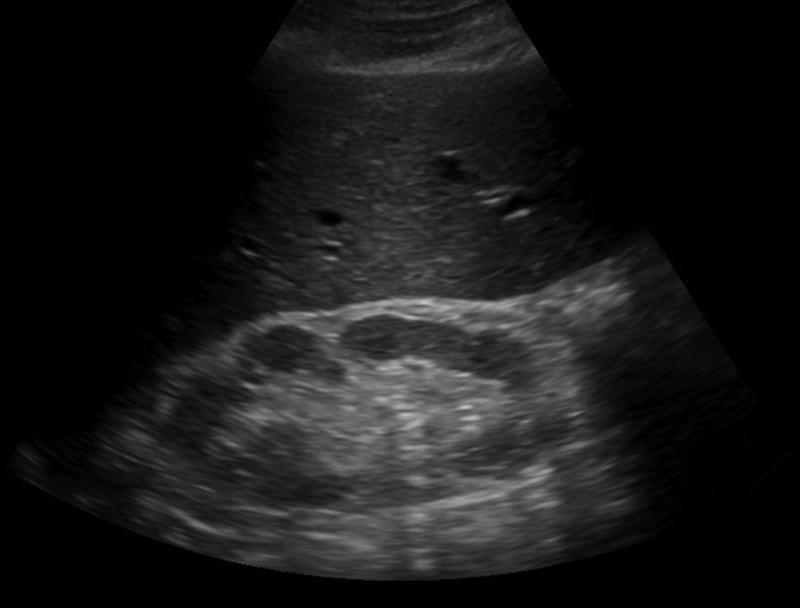

Adult Polycystic Kidney Disease

infant presents with renal dysfunction

Infantile Polycystic Kidney Disease

results from cystic dilation of the collecting tubules